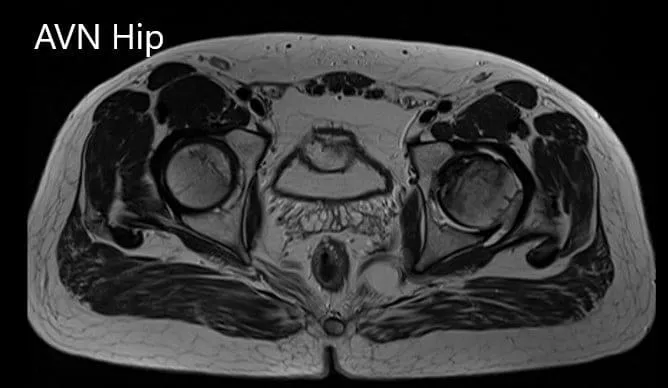

Imaging studies obtained in the form of an X-Ray suggested sclerosis of the left head of the femur. There were marked acetabulum changes. An MRI was further obtained suggesting avascular necrosis of the superior lateral head of the femur with changes in the acetabulum. There was marked hypointense areas on both T1WI and T2WIs.

T2WI coronal section of MRI showing AVN hip.

Axial sections of the T1WI and T2WI of MRI.